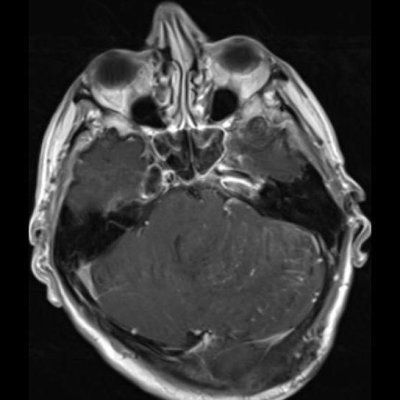

24 yaş, E

Baş ağrısı

Lhermitte-Duclos hastalığı (Dysplastic cerebellar gangliocytoma)